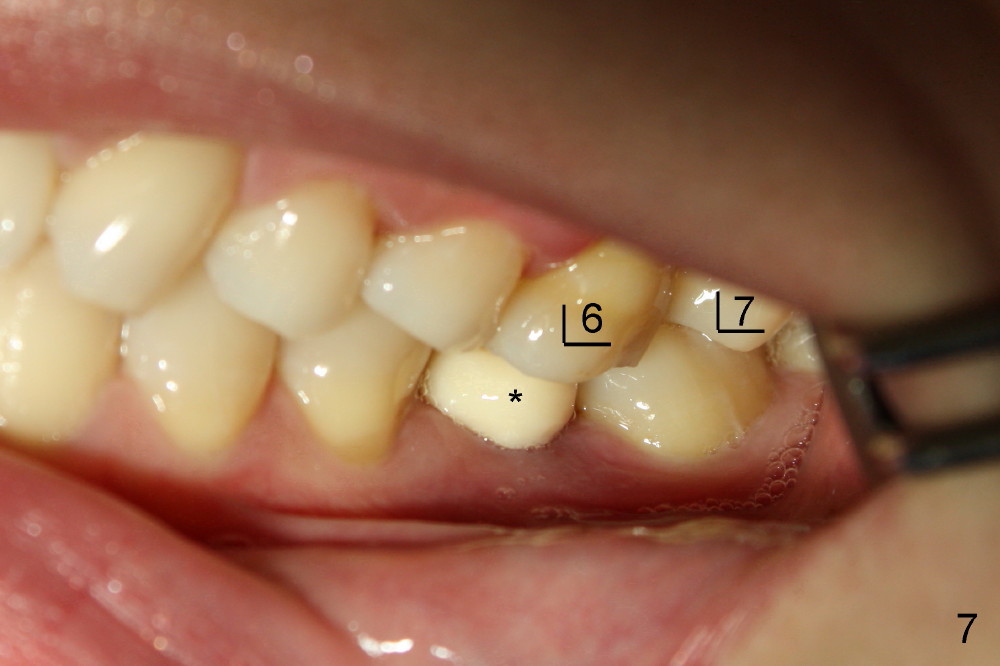

两周后,右下牙冠粘固,稍微调合,牙冠合面就穿孔了,向病人赔礼道歉,只好再预约重做,病人不满意的地方是牙冠与邻牙之间食物坎塞,重做牙冠还可能不能解决问题,只有矫正才能改变牙齿位置,倾斜度,而改正牙齿之间接触关系。不过先做左上,左下牙冠,制作也不容易,图六显示术前左上第一磨牙(*),好像supraeruption不厉害,但是咬合观显示左上第一磨牙的确往下移动不少(图七),星号(*)代表左下临时牙冠。没有任何其它选择,只好大刀阔斧磨左上第一磨牙(图八),这次大刀阔斧心情可不好,很辛苦。检查咬合,发现上下空间太大了(图九箭头),上次磨下颌基牙时太过分了。